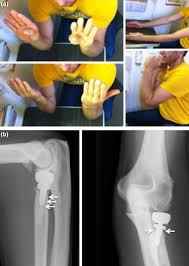

Undergoing arthroplasty for neglected femoral neck fractures at the 359 hospital of the people s liberation. The radial head arthroplasty consisted of first cementing the modular bipolar stem in place. Purpose the goal of arthroplasty is to restore the function of a stiffened joint and relieve pain. Joint resection involves removing a portion of the bone from a stiffened joint.

A bipolar articulation was then inserted and the kinematic pattern defined. Hemi means half and arthroplasty refers to joint replacement replacing the entire hip joint is called. Two types of arthroplastic surgery exist. A monopolar implant was created by placing a circumferential wire around the neck of the bipolar device and tightening it in a way to remove all visual evidence of motion fig.